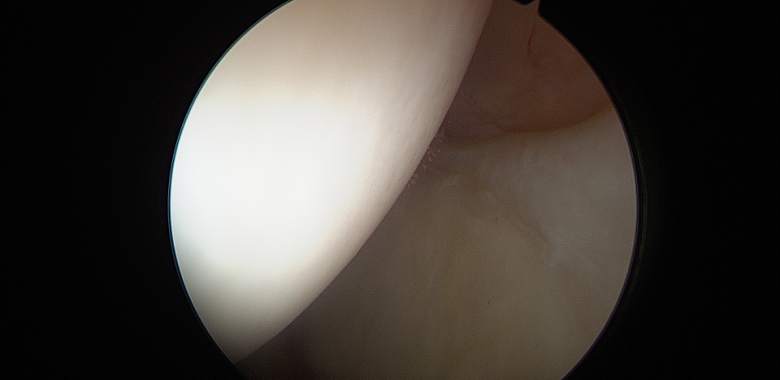

Η έγχυση στο ισχίο, αποτελεί μία καθιερωμένη τεχνική στα πλαίσια της συντηρητικής αντιμετώπισης της μηροκοτυλιαίας πρόσκρουσης. Παραδοσιακά, η λήψη απόφασης για αρθροσκόπηση ισχίου επηρεάζεται σε μεγάλο βαθμό από την ανταπόκριση του ασθενή στην έγχυση. Νέα μελέτη, όμως, έδειξε ότι το αποτέλεσμα της αρθροσκόπησης ισχίου δεν συναρτάται πάντα με το αποτέλεσμα της έγχυσης αυτής.

Σε μία νέα μελέτη, έγινε προσπάθεια να προσδιοριστεί η διαφορά του αποτελέσματος μετά από αρθροσκόπηση ισχίου, σε ασθενείς που ανταποκρίθηκαν, και σε αυτούς που δεν ανταποκρίθηκαν μετά από έγχυση ισχίου με στεροειδές.

Επρόκειτο για μία αναδρομική μελέτη ασθενών που υπεβλήθησαν σε πρωτογενή αρθροσκόπηση ισχίου, μεταξύ των ετών 2012 και 2014.  Οι ασθενείς χωρίστηκαν σε δύο ομάδες, με την πρώτη να αποτελείται από αυτούς που ανταποκρίθηκαν θετικά στην έγχυση, και τη δεύτερη, από αυτούς που δεν ανταποκρίθηκαν τελικά.  Για την εκτίμηση των αποτελεσμάτων χρησιμοποιήθηκαν οι συνήθεις κλίμακες αξιολόγησης του ισχίου. Συμπεριελήφθησαν 116 ασθενείς από την κάθε ομάδα, και έγινε επεξεργασία των αποτελεσμάτων με στατιστικές μεθόδους.  Δεν υπήρχαν διαφορές σχετικά με τα δημογραφικά, και άλλα γενικά στοιχεία των δύο ομάδων. Παρατηρήθηκε ότι και οι δύο ομάδες παρουσίασαν παρόμοια αποτελέσματα, μετά από την αρθροσκόπηση ισχίου, σε χρονικό διάστημα 10 ετών.

Οι συγγραφείς συμπέραναν ότι η ανταπόκριση μετά από έγχυση στο ισχίο με στεροειδές, δεν σχετίστηκε με διαφορές στα δεκαετή αποτελέσματα μετά από αρθροσκόπηση ισχίου, ή στο ποσοστό επανεγχείρησης. Έτσι, φάνηκε ότι ενώ η ενδαρθρική έγχυση στο ισχίο παραμένει ένα σημαντικό εργαλείο στην εκτίμηση της μηροκοτυλιαίας πρόσκρουσης, η έλλειψη θετικής ανταπόκρισης μετά από αυτήν δεν αποκλείει ένα θετικό αποτέλεσμα μετά από αρθροσκόπηση ισχίου.